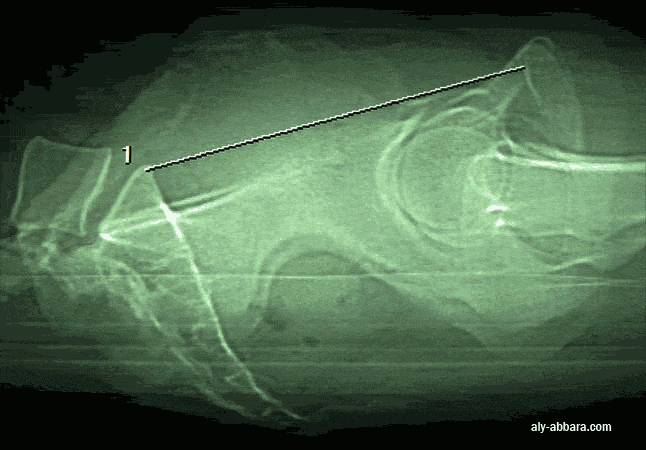

Diamètre promonto-rétro-pubien (PRP) (ou le diamètre conjugué vrai ; le diamètre sagittal utile de Pinard) : mesuré du promontoire au point le plus éminent de la face postérieure du pubis (culmen rétro-pubien). Valeur normale > 105 mm.